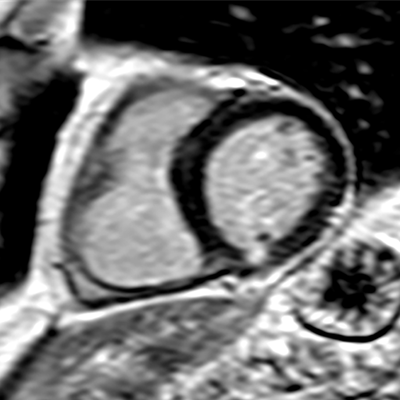

MRI provides excellent soft-tissue contrast, quantification of cardiac function and blood flow, as well dynamic perfusion imaging, and can be considered as the gold standard for many cardiac imaging applications. "In combination with PET, this may improve the assessment of myocardial viability and myocarditis, to name only two examples," he said.

However, PET/MR is still a relatively new introduction to hybrid imaging, and existing limitations are the subject of ongoing research. Notably, MR-based attenuation correction (AC) of PET data is an active field of research in PET/MR. "Attenuation correction in PET imaging is a precondition to obtain quantitative data about the metabolism of the radiotracer in different tissues, for example, the myocardium and/or lesions. In PET/MR, AC has to be performed in a fundamentally different way than AC in PET/CT, where the attenuation data is obtained by a CT scan," he noted.